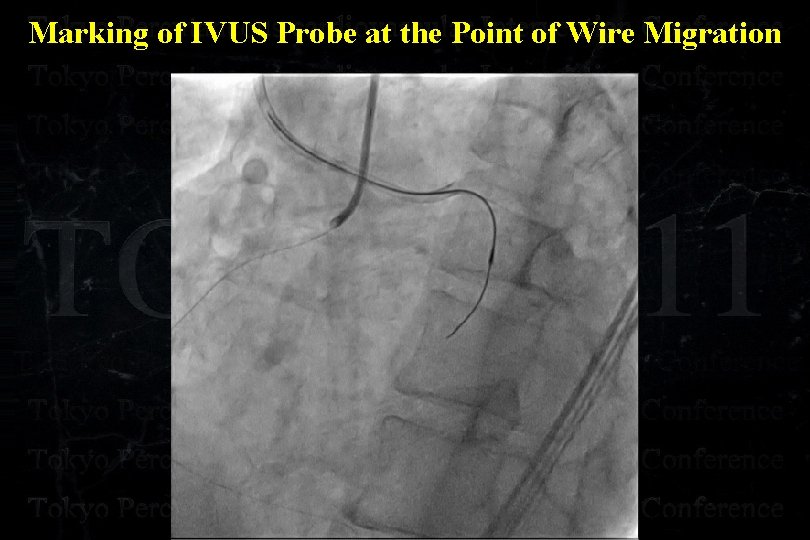

Marking of IVUS Probe at the Point of Wire Migration

Marking of IVUS Probe at the Point of Wire Migration LAO cranial RAO caudal